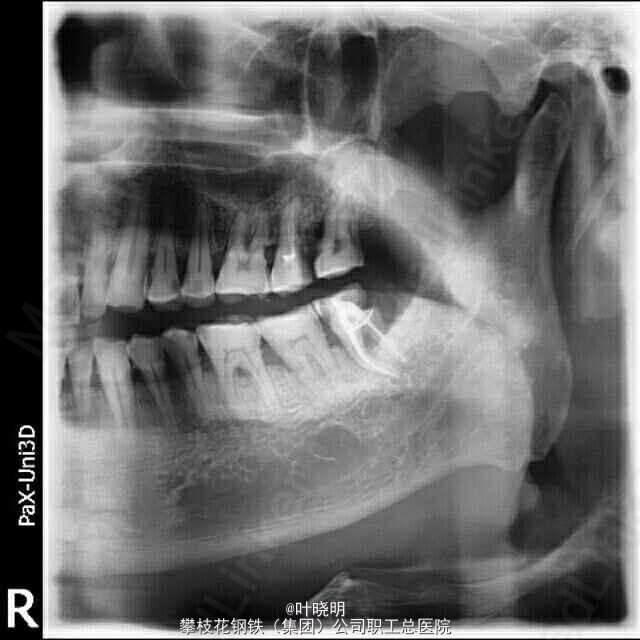

左下8根管治疗

38颊面深龋,探已穿髓,松(-),冷测敏感并持续数秒,叩(+-):有对合且关系良好。

诊断:38慢性牙髓炎急性发作 治疗:初诊局麻下扩穿髓孔,备洞置“三甲”失活剂,半月复诊去冠髓,摄根尖片见近中根弯曲向远中,拔髓封“CP”一W;复诊时先用不锈钢1O号K锉(21mm)预弯达根尖止点;再用S3镍钛锉配合EDTA对根管进行充分润滑;轻微施压使S3锉沿着根管走向向根尖推进,反复冲洗再封“Ca(OH)2” 一次,复诊时试尖根充并恒垫充填。